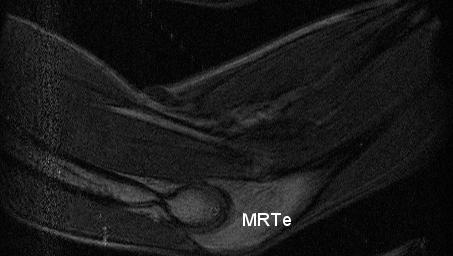

0.3T14cm磁気回路用のシールドルームレス対応の大型RFコイル(φ160mmx85mmH)の開発を行い、足部の撮像行った。被写体は健常男性足部。撮像シークエンスは3D-GE (TR/TE/FA = 40ms/5ms/90, matrix= 512 x 160 x 48, voxcel_size = 0.4 x 0.8 x 1.8 mm3, NEX=2)であり、限定されたFOVを考慮して足部の位置を3回移動させて3回画像取得した(Fig.1)。画像はImageJを用いて回転させて任意領域でトリミングを行い接合を行った。また、上肘の撮像を、既述の足部と同じ撮像シークエンスで取得した。掲示している肘画像は接合を行っていない生データの画像である(Fig.2)。この結果からギャップ14cmと人体用としては比較的狭いの磁気回路を用いた場合でも大きめの被写体の撮像ができる可能性が示された。

Fig.1.上腕の3D-GE画像。TR/TE/FA = 40ms/5ms/90, matrix= 512 x 160 x 48, voxcel_size = 0.4 x 0.8 x 1.8 mm3, NEX=2。